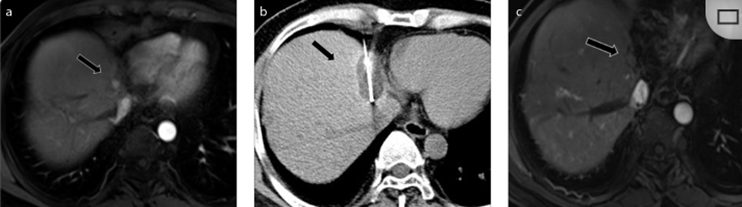

( a ) 軸向 MRI 和 ( b ) 軸向 CT 顯示肝S8段有一個16mm的病灶,鄰近肝緣。( c )冷凍消融期間CT顯示放置了2個冷凍探針,低密度冰球包圍病灶。(d)術后1個月隨訪 CT顯示冰球對應的壞死區(qū)域,未見復發(fā)。(e)術后6個月的CT,壞死區(qū)域縮小,未見復發(fā)。(f)與基線影像(g)相比,12個月后的FDG-PET/CT顯示未見FDG攝取。

(a)軸向CT顯示病變位置毗鄰心臟和上腔靜脈(黑色箭頭)。1個月后的軸向(e)和冠狀位(f)增強CT掃描顯示低密度區(qū)域,由于肉芽組織反應引起的邊緣增強。